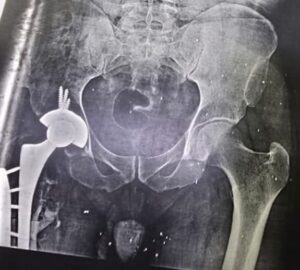

الصفحة الرئيسية محافظاتإنجاز طبي يُكتب لأول مرة بمستشفى قها التخصصي